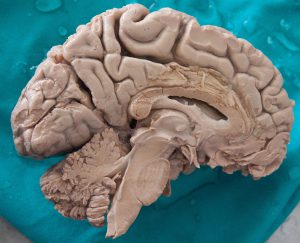

El cerebro humano pesa alrededor de kilo y medio, alberga cerca de diez mil millones de células llamadas neuronas, las cuales generan impulsos eléctricos para comunicarse entre sí, además de producir cambios químicos que permiten a dicho órgano llevar a cabo las funciones más sorprendentes, complejas y misteriosas del cuerpo humano, como son la generación de pensamientos o emociones, la imaginación, el lenguaje, el comportamiento, entre otras.